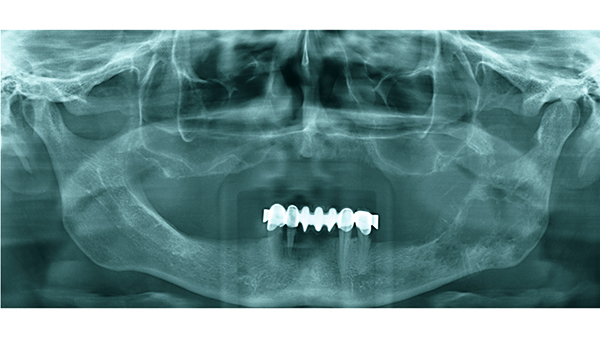

Befunde dieses RÖ-Bild

Panoramaschichtaufnahme. Zystischer Prozess im Unterkiefer links im Bereich der Schaltlücke in regio 36 ohne Lagebeziehung zum Zahnbestand.

Histologie: radikuläre Zyste. Diagnose: Residualzyste [nach Zahn- Extraktion]

Panoramaschichtaufnahme.

Zystischer Prozess im Unterkiefer links mit

Lagebeziehung zum wurzelgefüllten Zahn 37.

Histologie: radikuläre Zyste